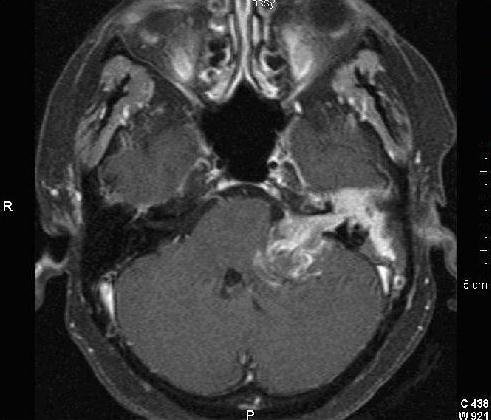

A superior sulcus tumor (a.k.a Pancoast tumor) can invade the lower trunk of the brachial plexus and the sympathetic fibers arising from T1 (a.k.a Pancoast’s syndrome). While thoracic outlet syndrome can affect the lower trunk, ptosis, and myosis are not characteristic findings. Raeder’s paratrigeminal neuralgia is associated with ptosis and myosis and facial pain. It would not explain persistent medial arm pain. Similiarly neither medial cord inflammatory injury nor ulnar nerve trauma would account for the ptosis and myosis observed.